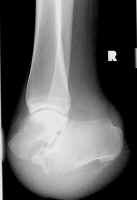

These images show an amputation through the calcaneal-cuboid and talo-navicular joints

(Chopart level).

Selected images of different patients showing the Chopart amputation.